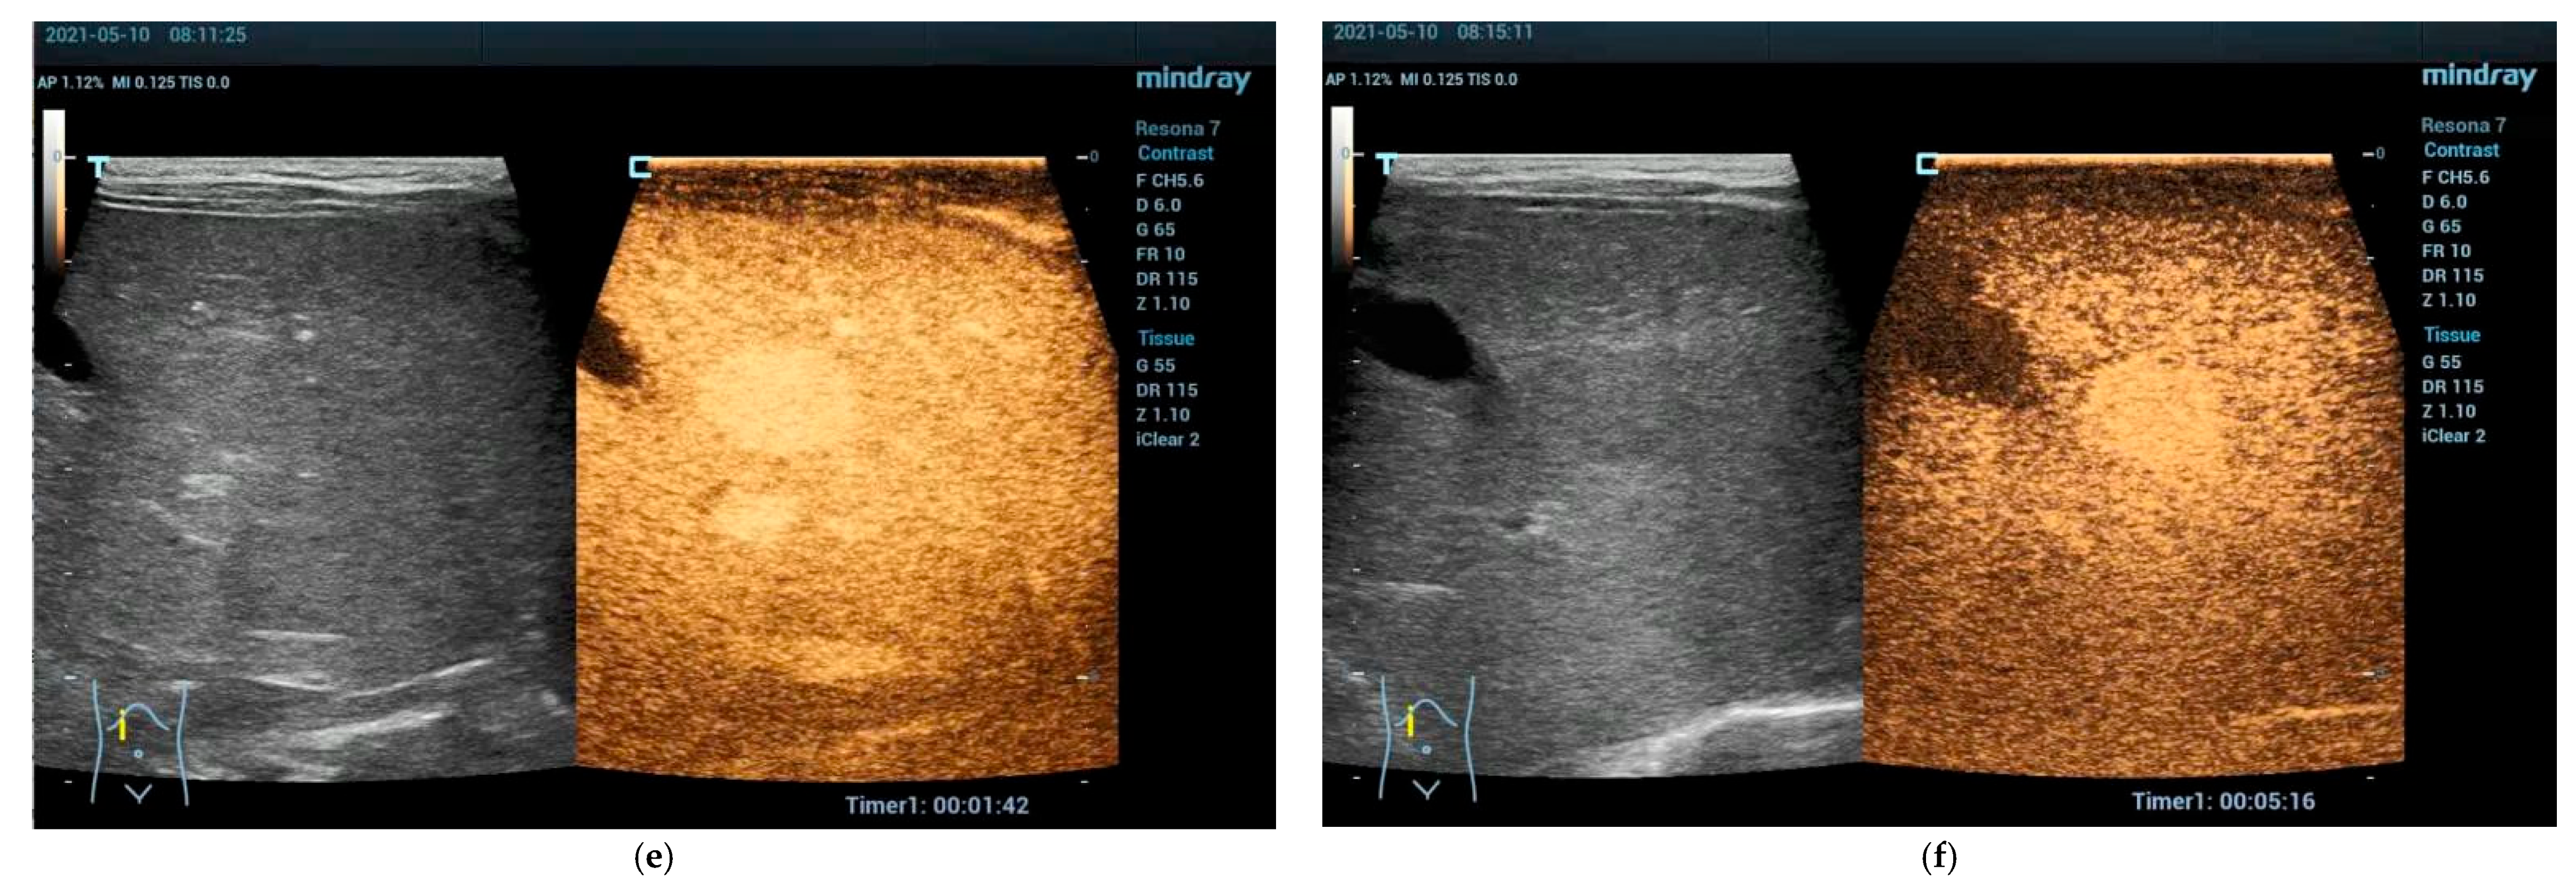

Focal Nodular Hyperplasia (FNH)

5.1. Focal Fatty Sparing (FFS)

5.2. Focal Fatty Infiltration (FFI)